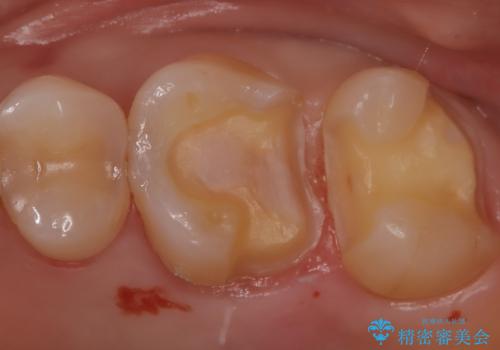

【セラミックインレー】適合の良いセラミックインレーを入れたい。

- 毎回フロスが引っかかることを気にされており、改善のため適合の良いセラミックインレーで修復しました。

以前に他院で詰め物をいれた時は、フロスが毎回ちぎれて大変だったそうですが改善して喜んでおられました。

当院のセラミックインレーは必ずラバーダムを使用して接着しています。